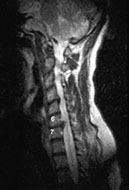

Sagittal magnetic resonance image of the cervical spine. This image reveals a C6-C7 herniated nucleus pulposus.

- MRI has become the method of choice for imaging the neck to detect significant soft-tissue pathology, such as disc herniation. The American College of Radiology recommends routine MRI as the most appropriate imaging study in patients with chronic neck pain who have neurologic signs or symptoms but normal radiographs. [24] MRI can detect ligament and disc disruption, which cannot be demonstrated by other imaging studies. The entire spinal cord, nerve roots, and axial skeleton can be visualized. This study is usually performed in the axial and sagittal planes.